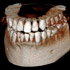

Alles umfassend - 2D und 3D in einem

Das Röntgengerät X-ERA SMART vereint Technologie und Innovation auf eindrucksvolle Weise. Es erlaubt sowohl 2D als auch 3D Bildbearbeitung. Maximaler Bedienungskomfort und Effektivität wird durch einen großen Touchscreen, eine übersichtliche und bedienerfreundliche Struktur für ein schnelles und fehlerfreies Arbeiten erreicht.

X-ERA SMART 3D. Das System für drei Technologien

X-ERA SMART wurde als das ideale Gerät für 3D und Panorama Imaging entwickelt. Mit schmalem und kompaktem Design und exzellenter Funktionalität verfügt es über alle Innovationen, die Zahnmediziner von einem modernen Röntgengerät erwarten. Anschaffung und Rentabilität erlauben es jeder Praxis, mit einem solch hochwertigen diagnostischen System zu arbeiten. Das 3D-Panorama System kann jederzeit mit einer Fernröntgenausstattung zusätzlich ausgestattet werden.